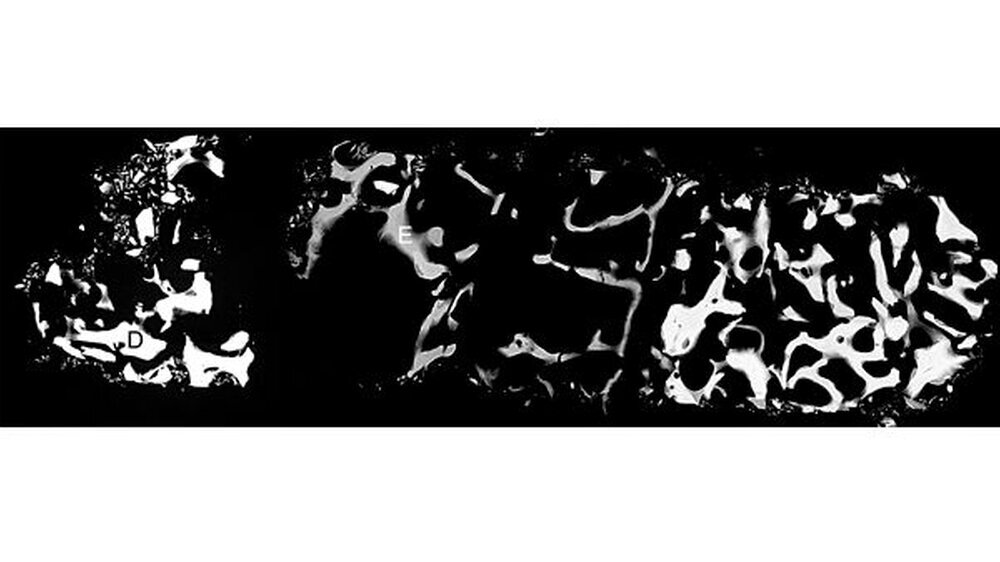

Ayna dokumentierte die chirurgisch aufwendige Behandlung eines Duisburger Patienten. Dabei handelte es sich um den Knochenaufbau in der Kieferhöhle, den Sinuslift. 14 Jahre nach dem Einsatz des anorganischen Rinderknochen-Materials (ABBM) führte Ayna eine histologische und eine mikroradiografische Untersuchung des eingelagerten Materials durch.

Ergebnis: Das Material wurde auch nach diesem langen Zeitraum nicht vom Körper aufgelöst. Vielmehr kam es zu einer erfolgreichen Knochenneubildung. Aynas Untersuchung weist in dem aufgebauten Knochenbereich einen Eigenknochenanteil von mindestens 14 Prozent nach. Die histologischen Untersuchungen lassen darauf schließen, dass der Sinuslift in den zentralen Bereichen aus vitalem Knochen besteht.